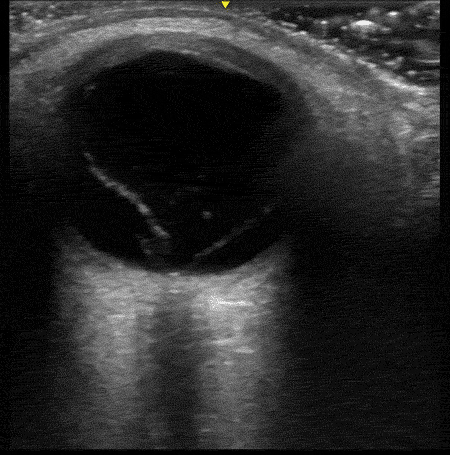

Clip 2: same eye as clip one, but with the gain turned all the way up

Notice what a difference the gain setting makes. There is clearly a vitreous detachment that was completely invisible at the default gain setting